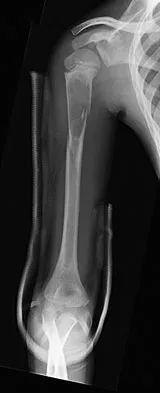

An 11-year-old boy has right shoulder pain and has been unwilling to use the arm after throwing a baseball in a Little League game 3 weeks ago. Examination reveals upper arm and shoulder tenderness with swelling. A radiograph and MRI scan are shown in Figures 27a and 27b. Management should consist of

The radiograph is consistent with a unicameral (simple) bone cyst. The MRI scan reveals that the cyst is juxtaposed to the physis and therefore can be classified as active (latent cysts are more than 1 cm away from the physis). Active cysts are treated with aspiration and steroid injection, although repeated injections may be necessary. Curettage and bone grafting results in more reliable healing but may lead to growth arrest in active cysts. Iannotti JP, Williams GR: Disorders of the Shoulder: Diagnosis and Management, ed 1. Philadelphia, PA, Lippincott Williams & Wilkins, 1999, pp 945-946.

- Malawer MM: Tumors of the shoulder girdle: Techniques of resection and description of surgical classification. Orthop Clin North Am 1991;22:7-35.